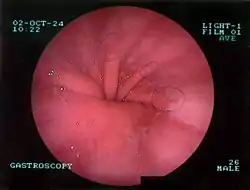

Upper GI endoscopy depicting hiatal hernia

The diagnosis of a hiatal hernia is typically made through an upper GI series, endoscopy or high resolution manometry.[11]